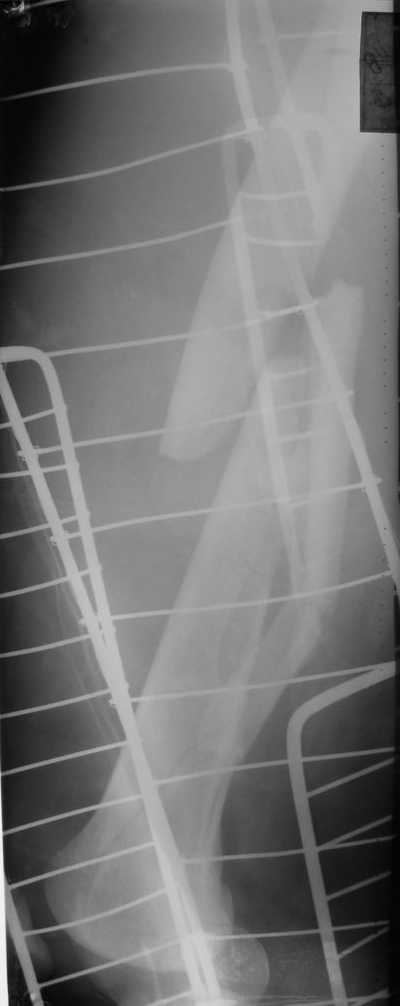

Лечился в ЦРБ. К нам поступил вчера. Имеется оскольчатый перелом диафиза левого бедра, перелом медиального мыщелка, краевой перелом надколенника. У нас, кроме того, выявили перелом шейки бедра. Перелом закрытый, имеется рана в в/3 голени(ниже уровня бугристости б/берцовой кости)без признаков инфицирования.Планируем закрыто фиксировать мыщелок и надколенник винтами, затем закрыто заштифтовать бедро. Вопрос возник по перелому шейки: что предпочесть - длинный PFN или DFN + DHS на шейку?Буду благодарен за ценные советы.С уважением, Станислав Дмитриев.

Заранее приношу извинения за качество снимков. То что есть - либо из ЦРБ, либо сделано в приемном покое, где дежурят рентгенлаборанты различной квалификации. Завтра постараемся сделать снимки всего бедра на длинные кассеты в 2 проекциях. Сейчас больной на скелетном вытяжении. Состояние стабильное.